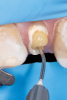

Fig 11. Channel preparation using color-coded drill.

Figure 11

After determination of the desired post channel length (one-half to two-thirds the length of the canal), a dental dam was placed using the modified dam technique. The gutta-percha was removed with a series of preshaping instruments (Gates Glidden drills). The channel preparation for a prefabricated fiber-reinforced post (ie, the fiber-optic post system referred to earlier) was performed using a color-coded drill from this post system, establishing the desired intraradicular length and size for the selected post (Figure 11). The prepared channel was rinsed with water and dried with an endodontic paper point.